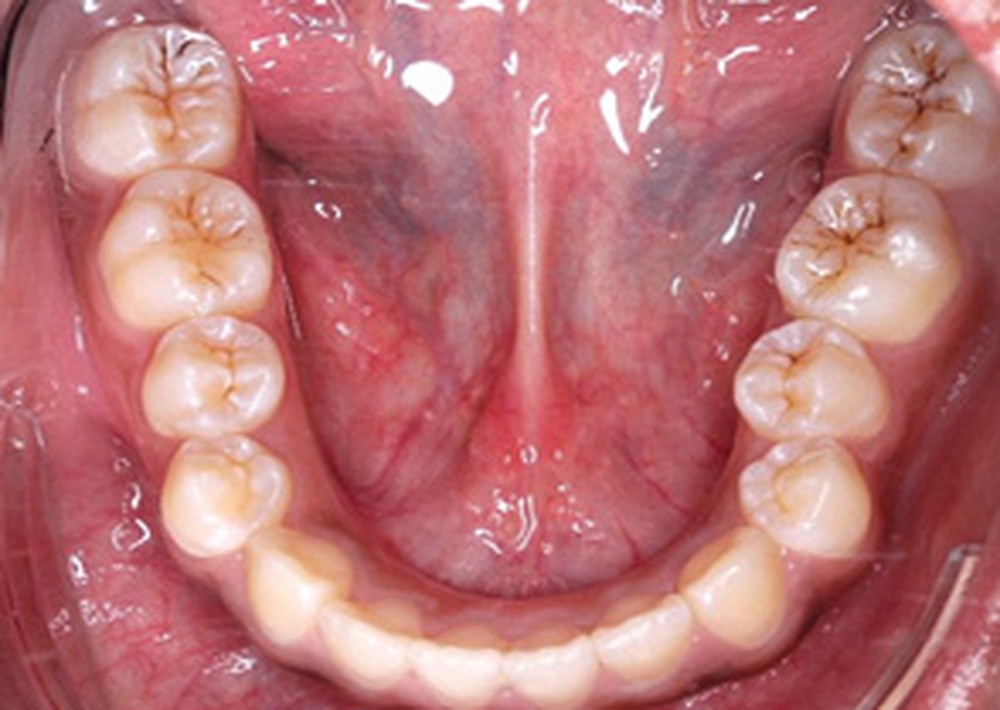

L’examen clinique endo-buccal révèle une denture adulte jeune avec un inversé d’articulé antérieur de 13 à 23, des tatouages gingivaux ethniques et des taches de décalcifications, un parodonte sain mais un brossage insuffisant.

L’arcade maxillaire est en V et la voûte palatine profonde. L’arcade mandibulaire a une forme en U (non-concordance des formes d’arcade) et présente des malpositions des dents cuspidées. La médiane mandibulaire est décalée à gauche de 2 mm ; le recouvrement antérieur est de 2 mm ; les molaires sont en classe III avec un surplomb inversé.

Lors de la réévaluation post-chirurgicale, l’examen exo-buccal montre peu de changement, excepté l’occlusion et l’harmonie labiales retrouvées. Le surplomb et le recouvrement sont normalisés et le brossage amélioré. Les formes d’arcade sont concordantes, les médianes inter-incisives recentrées et les molaires et canines en classe I.

Les finitions orthodontiques d’intercuspidation et de parallèlisation des axes ont été réalisées sur arcs TMA .019x.025 et élastiques interarcades de classe III 6 mm 4 oz puis triangle d’intercuspidation 4 mm 6 oz. Enfin, le dispositif de contention a consisté en fils collés 2-2 maxillaire et 3-3 mandibulaire et gouttière thermoformée maxillaire.